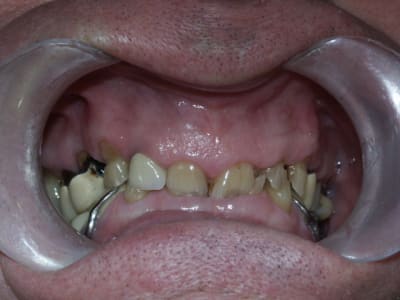

Qu'est ce que je peux proposer comme plan de traitement?

j'avoue que je suis un peu paumé...

Le constat est le suivant, corrigez-moi si je me trompe:

on a eu des extractions non compensées à la mandibule qui ont provoquées des égressions des dents maxillaires postérieures.

une abrasion +++ du bloc antérieure avec égression "physiologique" au fur et à mesure de l'usure.

On a ainsi un décalage important (comme une marche d'escalier) de la courbe d'occlusion (Spee) entre le secteur antérieur et postérieur.

La difficulté de la thérapeutique consistera à rattraper le mieux possible ce décalage pour avoir une courbe d'occlusion "harmonieuse".

Il conviendrait d'augmenter la DV partout mais on risque de se retrouver avec les difficultés suivantes:

- en postérieur, l'augmentation de DV sera importante et on risque de vite se retrouver avec des couronnes avec un rapport couronne / racine défavorable.

- en antérieur, le gain de DV obtenu sera plus faible du fait de l'égression physiologique des dents. Le dilemne est de savoir si cela permettra d'avoir assez de place pour faire des couronnes.

Pour gagner un peu de hauteur sur les dents antérieures pour les futures CCM, je pensais faire des gingivectomies. Les bruxos ont souvent un parodonte en béton avec de la GA à revendre, favorable à cette technique. Cela permettrait de limiter l'augmentation de DV. Le seul truc qui coince c'est que le patient n'a pas des racines très longues.

Il faudra effectivement faire montage sur artic + waxup pour voir ce qu'on peut faire exactement parce que là... pffff!